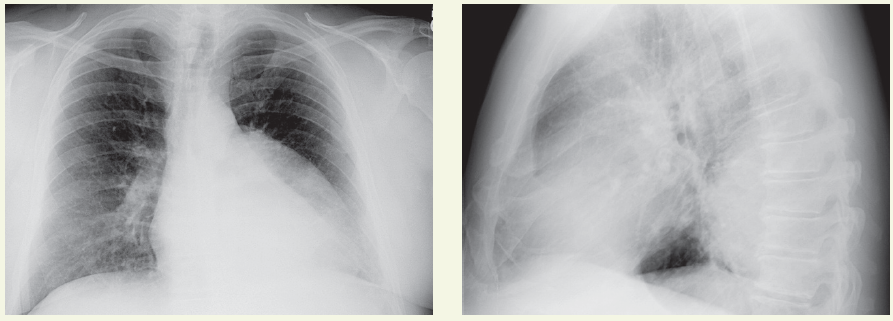

COPD

Amir A. Zeki, MD, MAS; Samuel Louie, MD

A patient with a history of hay fever and cigarette use presents with wheezing, a cough, and dyspnea. Is it asthma or COPD?